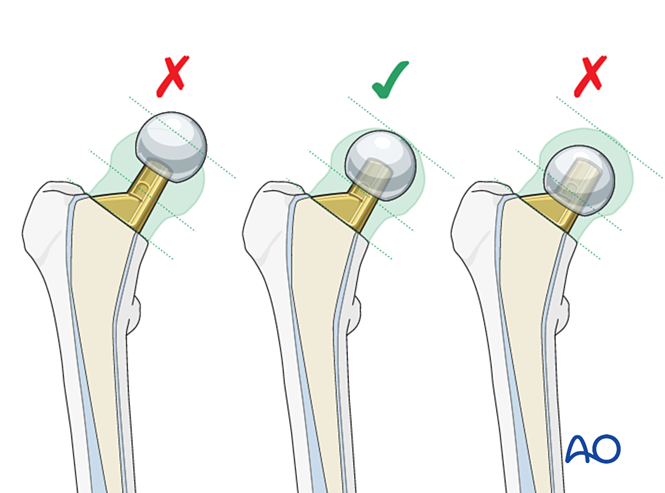

假体置入与冠状面对位

目标:假体柄中立位置入股骨髓腔。避免因偏心力致假体颈内翻。

图示骨水泥柄正确对位(左)与内翻对位(右,易致松动)。